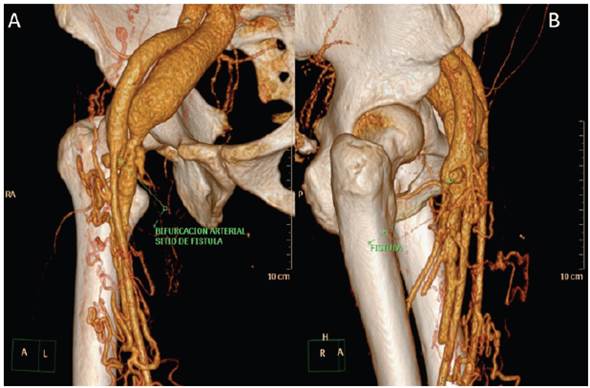

This was a 42-year-old male who underwent surgery for transposition of the great arteries as a child. Twenty years later a catheterization through the right deep femoral artery was performed. Over the last five years he has had edema with a change in color of his right foot 50 seconds after going from a lying to a standing position (Figure 1). Computed tomography angiography corroborated the diagnosis of an arteriovenous fistula (AVF) in the right femoral system (Figures 2 and 3). He was referred to vas cular surgery for stent placement.